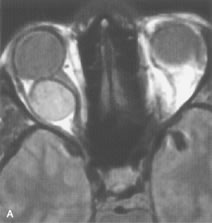

Extraocular muscle enlargement in patients with thyroid-associated orbitopathy is demonstrated equally well with CT and MRI studies. However, the superior tissue contrast on MR images reveals better details of the relationships of the optic nerve to the thickened muscles at the orbital apex (Fig. 16).50 In addition, MRI may be able to differentiate between muscles that are enlarged as a result of edema and active inflammation and those enlarged because of fibrosis by their T2 relaxation times.21 Quantitative MRI was not found to be accurate in predicting the success of low-dose orbital irradiation.51 However, a muscular index relating the diameters of the rectus muscles to the bony orbital dimensions was useful in predicting optic nerve compression.52

Fig. 16. A-C, T1-weighted MR scans obtained with a high-resolution surface coil demonstrate fusiform enlargement of the extraocular muscles. The medial, lateral, and inferior rectus muscles are especially involved. Note the relative sparing of the tendinous insertions, a finding characteristic of this disease process, as well as fatty infiltration of the lateral and inferior rectus muscles. There is marked proptosis, best visualized on the sagittal image (A), and mild crowding of the optic nerve at the orbital apex.